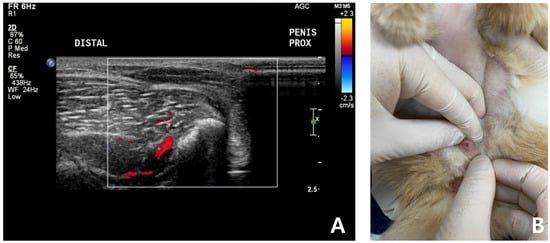

Complete blood count (CBC) was normal except for mild lymphopenia (1.24 × 109 cells/L) (reference interval [RI]: 2–7.2) and mild eosinopenia (0.12 × 109 cells/L) (RI: 0.3–0.7). Serum electrolyte concentration, serum biochemistry, gas analysis, and total T4 revealed no abnormalities except for elevated Feline serum amyloid A (FSAA) level (23 μL/mL) (RI: 0–10) and mild hyperglycemia (171 mg/dL) (RI: 73–134). Urethral catheterization revealed complete patency. Urinary samples collected by ultrasound-guided cystocentesis showed no abnormal laboratory urine test results and a negative result on bacterial culture. Abdominal radiography (XPLRER-900, Medien International Co. Ltd., Anyang, Korea) revealed edema of the perineal region. A cutaneous mass with fat opacity was also detected in the inguinal regions; this was later suspected to be a lipoma (Figure 2). Ultrasonography performed using Philips iU22 SonoCT system (Philips Ultrasound, Bothell, WA, USA) revealed that the erect, swollen penis’s parenchyma was homogenous and hyperechoic. The penile cavernosal artery was not clearly identified by color-flow Doppler ultrasonography with the lowest Nyquist limit range of −2.5–2.5 cm/s (Figure 3). Ultrasound-guided fine needle aspiration of the left inguinal mass identified lipid droplets before staining, and single large clusters of well-differentiated adipocytes with Diff-Quick staining were observed under a microscope.

Despite non-detectable blood flow in corpora cavernosa in color-flow Doppler examination, based on its history and other symptoms (21 days of persistent soft erection without severe pain), the cat was diagnosed with non-ischemic priapism.

After 7 days, the cat was brought to the animal hospital for physical examination and urogenital ultrasound recheck. FSAA, which showed an elevation at the first presentation, declined to the normal reference range. Physical examination and urogenital ultrasonography revealed significant pain reduction and reduced swelling of the penis. The penis was no longer enlarged or, hard, and it retracted into the prepuce well (Figure 4). According to the owner, the patient was bright and responsive, but seemed less energetic after the prescribed oral medication.

Color-flow Doppler ultrasound scanning is also an important diagnostic tool that enables clinicians to confirm cavernosal arterial blood flow and the existence of a fistula [19,30]. Sonographic characteristics of priapism have been reported in veterinary medicine [8,18]. A penile Doppler study in ischemic priapism displays absent cavernosal blood flow and low echogenicity resulting from sinusoidal thrombosis [30]. In human, non-ischemic priapism is characterized by normal or raised cavernosal arterial blood flow with high diastolic velocities [30]. In this case, no cavernosal arterial flow was identified, even with a low Nyquist limit (−2.5–2.5 cm/s) in the color flow Doppler study due to the small penis size in the feline. Generally, the absence of cavernosal arterial blood flow is a feature of the ischemic priapism [1,2,3]. However, the vessel’s inner diameter could be the factor that can not be detected by color-flow Doppler ultrasound scanning [31]. Considering anatomical limitations of the feline penis, we speculated that the vessel diameter could have been the reason. Further studies are needed because this case report first described the erected feline’s penile ultrasound.

Figure 3. Ultrasonography in a cat with non-ischemic priapism (A) swollen penis with homogeneous parenchyma; (B) The color-flow Doppler examination did not clearly identify penile cavernosal artery blood flow due to the small size of the feline penis.

Figure 4. Follow-up ultrasound examination of a cat with non-ischemic priapism after complete clinical resolution of persistent soft erection. No significant penile cavernosal artery blood flow was detected due to the anatomical limitation of feline penis (A). Penis was no longer enlarged, not hard and retracted into the prepuce well (B).